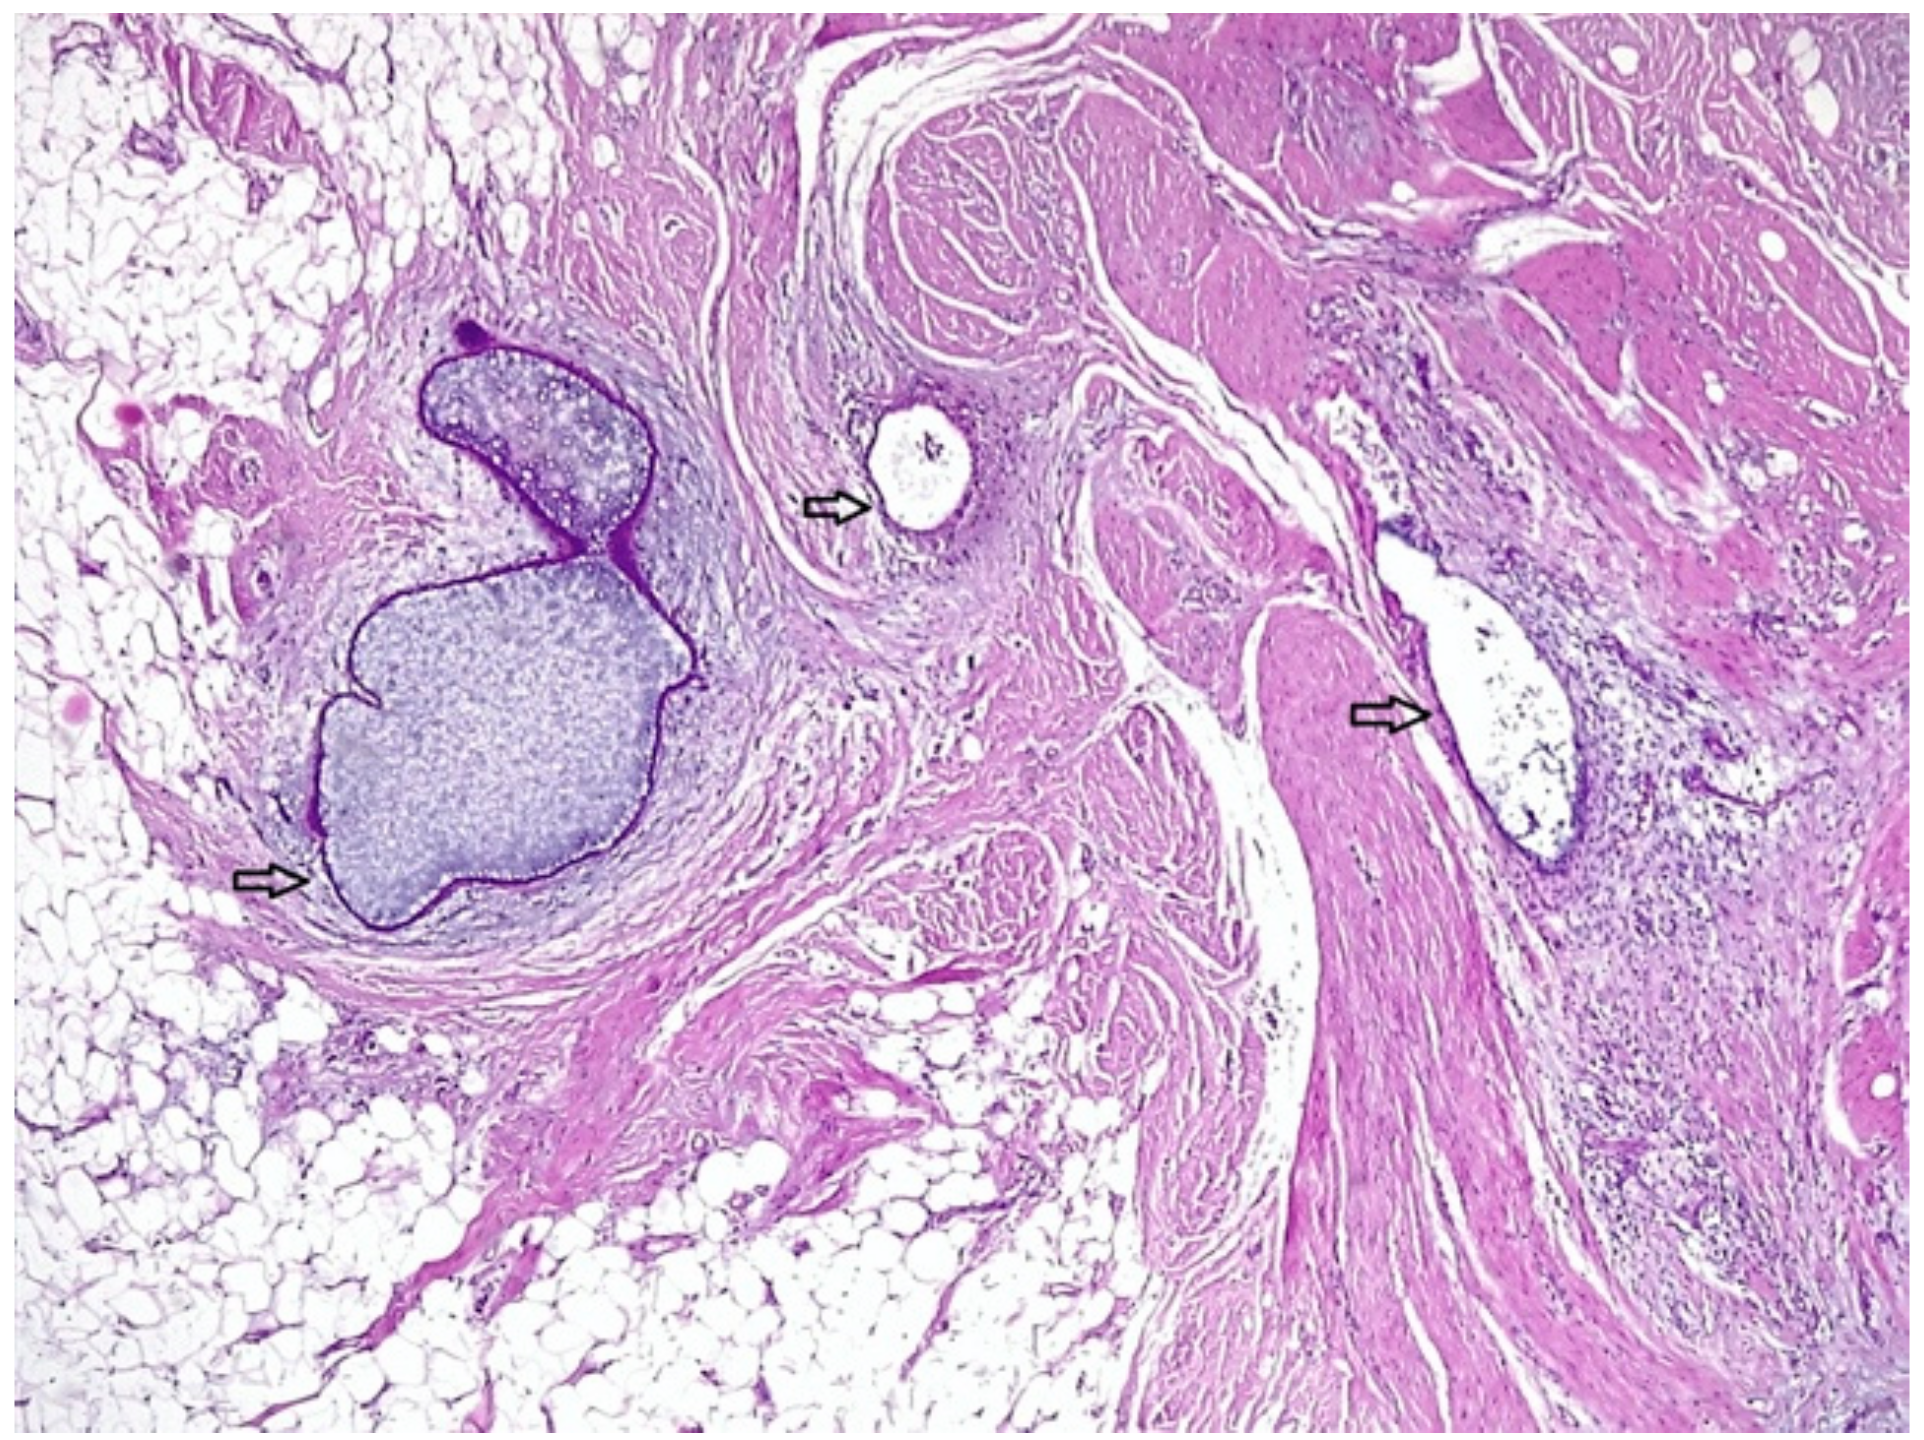

2.1. Case 1